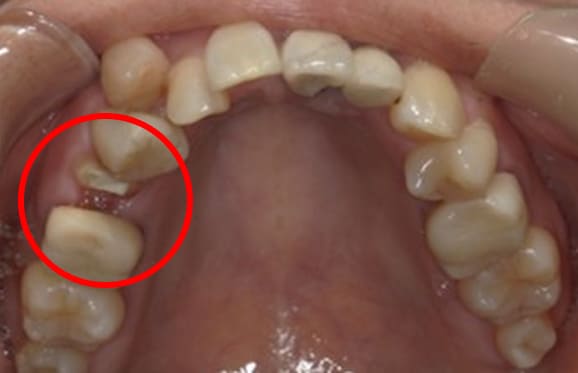

● C4を超え歯根までの虫歯を抜歯、スペースを利用して歯並び全体を整えた症例

藤沢デンタルオフィスの虫歯や破折で抜歯後の部分矯正